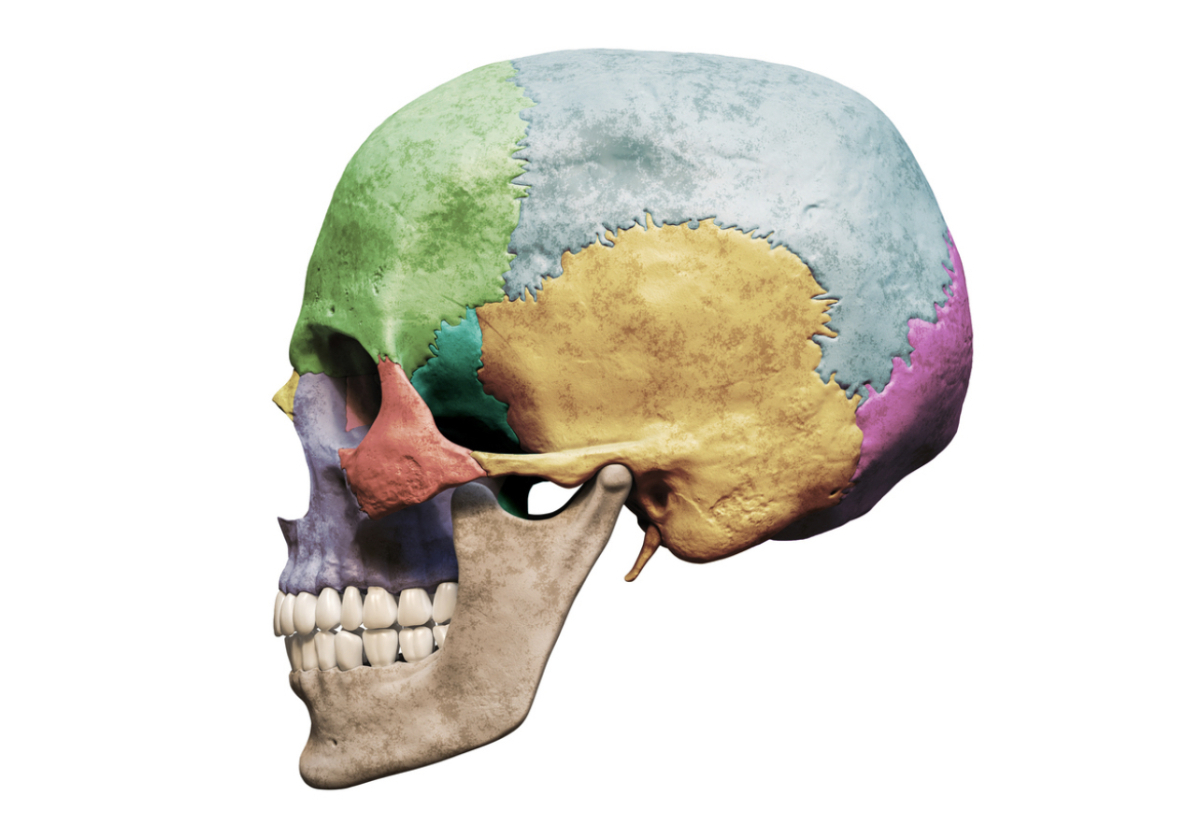

Anatomia twarzy

Ta lekcja pokazuje budowę twarzy w kontekście pracy kosmetologa. Zrozumienie układu tkanek, mięśni i struktur anatomicznych pozwala wykonywać zabiegi świadomie, bezpiecznie i z większą precyzją, co bezpośrednio przekłada się na efekty oraz komfort klienta.

- warstwowa budowa twarzy i jej znaczenie w pracy zabiegowej